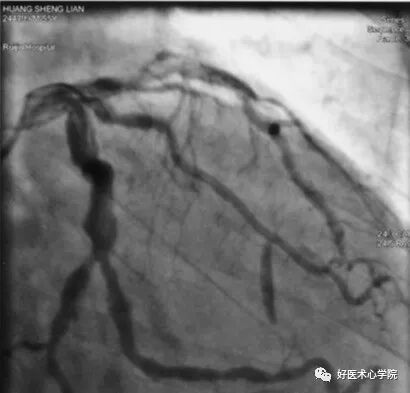

左前斜位:观察右冠全长,但难以看到远段分叉。

此时可以加足位可以观察。

• 冠的左前斜位——右冠似字母 “C”

造影导丝是什么珍藏 冠脉造影从流程到诊断,基础必备!_https://www.jmylbn.com_新闻资讯_第62张